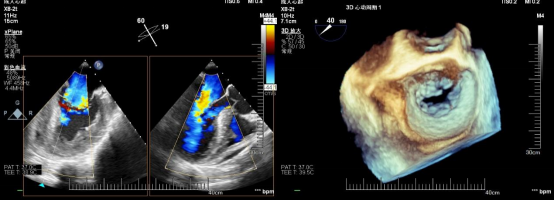

在患者全麻状态下经股静脉置管、经食道超声(TEE)引导房间隔穿刺后置入导引鞘管,手术团队将夹合器精准送达二尖瓣反流区。在TEE及X线引导下,手术团队利用二尖瓣夹(Mitraclip)准确捕获二尖瓣叶,试夹闭后经过超声证实夹闭有效,释放成型夹。术后超声评估,二尖瓣口仅见轻微反流,反流情况明显改善,患者各项生理指标正常,Mitraclip手术高质量完成。患者于术后第3天顺利出院,出院前检查患者二尖瓣反流各项参数指标恢复都超出了预期效果。

术前心超